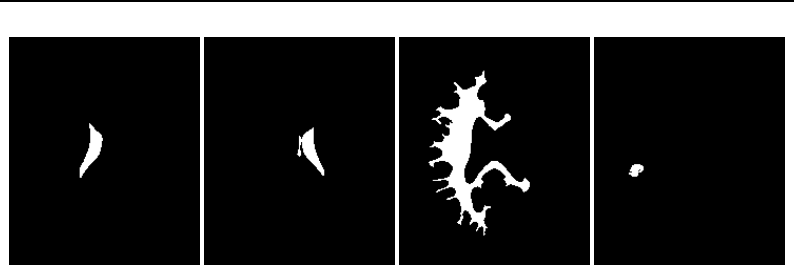

The National Library of Medicine Insight Segmentation and Registration Toolkit, shortened as the

Insight Toolkit (ITK), is an open-source software toolkit for performing registration and segmenta-

tion. Segmentation is the process of identifying and classifying data found in a digitally sampled

representation. Typically the sampled representation is an image acquired from such medical instru-

mentation as CT or MRI scanners. Registration is the task of aligning or developing correspondences

between data. For example, in the medical environment, a CT scan may be aligned with a MRI scan